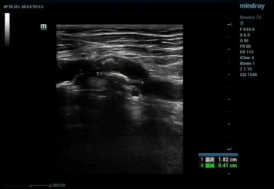

用药效果:丹蛭降糖胶囊对2型糖尿病合并下肢大血管病变治疗前后下肢多普勒超声比较

治疗前

基础降糖治疗患者治疗后下肢多普勒超声图无明显改善,基础治疗的基础上加用丹蛭降糖胶囊口服患者治疗后下肢多普勒超声图显示下肢动脉内-中膜厚度稍下降,斑块面积稍有缩小。